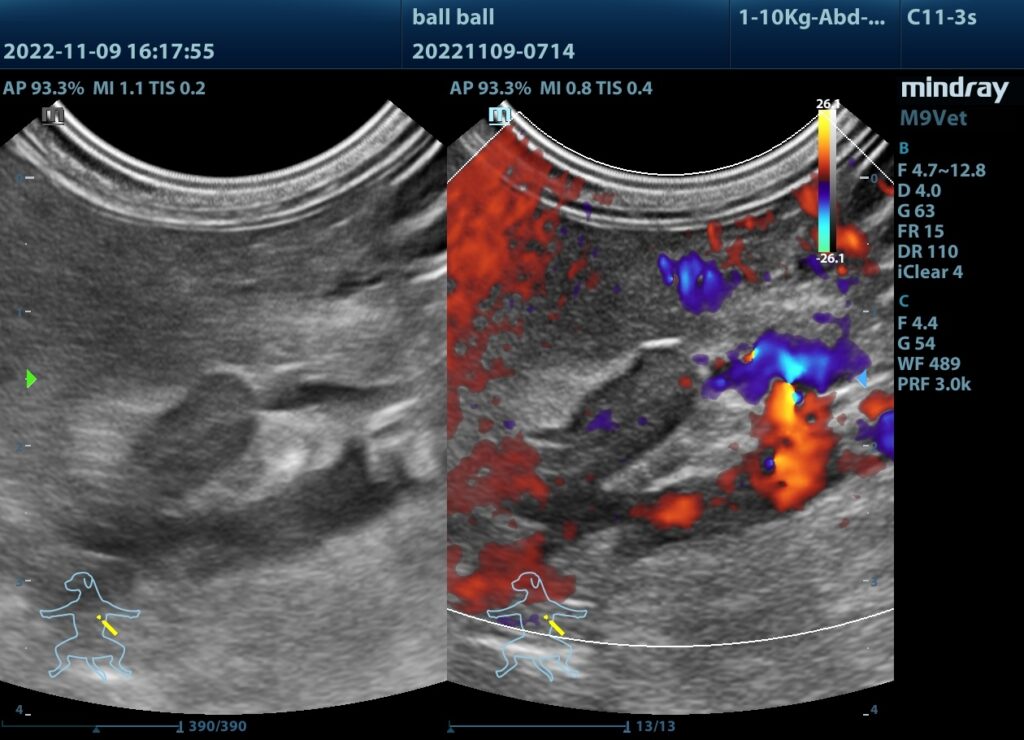

(2)超音波看見腫大的腎上腺。

腫大的腎上腺